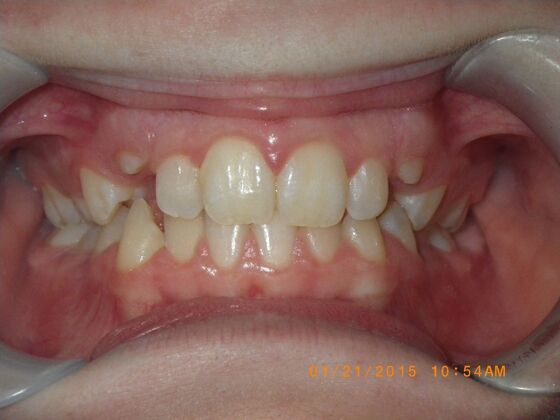

Orthodontics: Case 10

Description

This case presents with a dental midline discrepancy. The upper incisors are tipped toward the palate, which prevents the lower incisors from establishing proper arch form. The upper right molar has drifted forward, causing the upper midline to be skewed to her left. By distalizing the upper left molar, we can correct the midline discrepancy. Lastly, both upper and lower arches need expansion. All of this was completed with conventional straight wire appliances within 2 years.